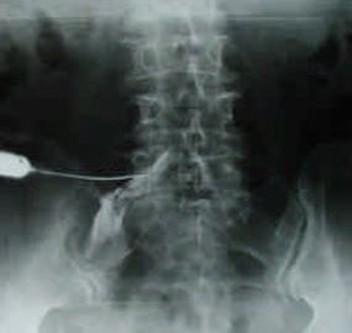

・ブロック注射

仙骨硬膜外ブロック注射は尾てい骨付近から注射し、神経根ブロックは痛みの原因となっている神経をピンポイントでブロックする方法です。ブロック注射は、痛みの軽減だけでな

く、どの神経が原因となっているかを特定する診断にも役立ちます。特に、透視装置(レ

ントゲン)を使用することで、より精度の高い神経根ブロックを行うことが可能です。